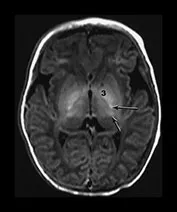

- MRI findings:

- DWI: Restricted diffusion (earliest sign, within hours).

- T1: Absent normal PLIC T1 hyperintensity (poor prognosis).

⭐ Deep grey matter (basal ganglia, thalami) injury on MRI in term neonates with HIE signifies severe insult and predicts adverse neurodevelopmental outcomes, especially if associated with lactate peak on MRS and restricted diffusion on DWI.